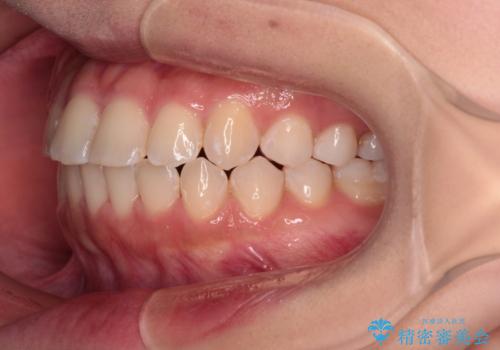

- 前歯のデコボコを気にして来院された患者様です。

マウスピース矯正のような自己管理の煩わしさがなく、早く治療を終えたいとのことで、ワイヤー装置による矯正治療を行うこととしました。

当初予定通り、1年で治療を終えることができました。